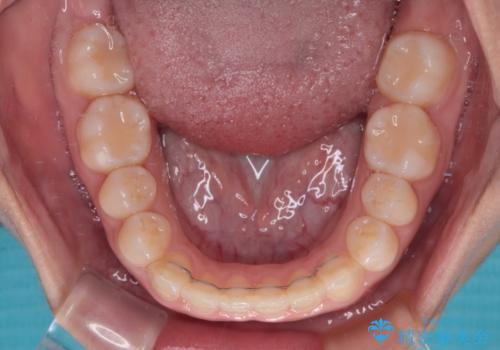

前歯のクロスバイトを改善 インビザライン・モデレートによる矯正治療

- 上下前歯のクロスバイトと叢生を気にして来院された患者様です。

インビザラインでの治療を希望されていて、デコボコの程度が中等度であり、安価なパッケージにて対応可能と判断されたため、インビザライン・モデレートを用いて矯正治療を行うこととしました。